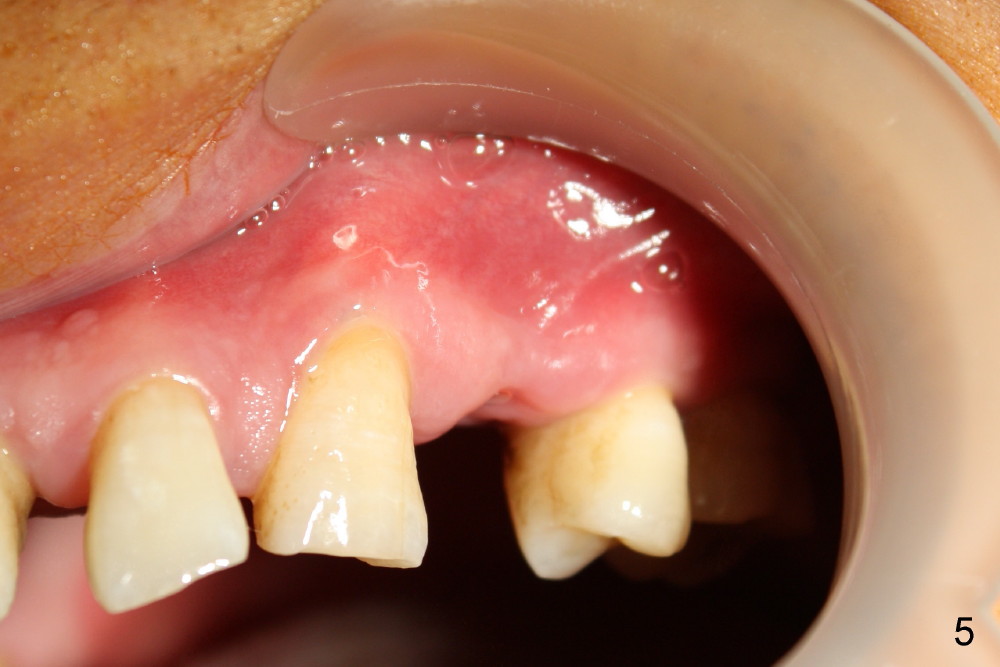

Dear Drs. Dunson and Borgner: Thank you for support. Fig.5 and 6 taken immediately prior to surgery show that the healing socket is elliptical (arrowhead). After D1 and D2 channel formers, D2 thin socket former is tapped in (Fig.7). The osteotomy needs to be redirected as shown by the black line. D2 implant is being inserted with Synthograft applied to the 1st two threads (Fig.8) and is in place (Fig.9,10). But the implant is not as stable as expected. There is a gap mesial to the implant (Fig.10 arrowhead), which is most likely created by re-directing the osteotomy with channel and socket formers.